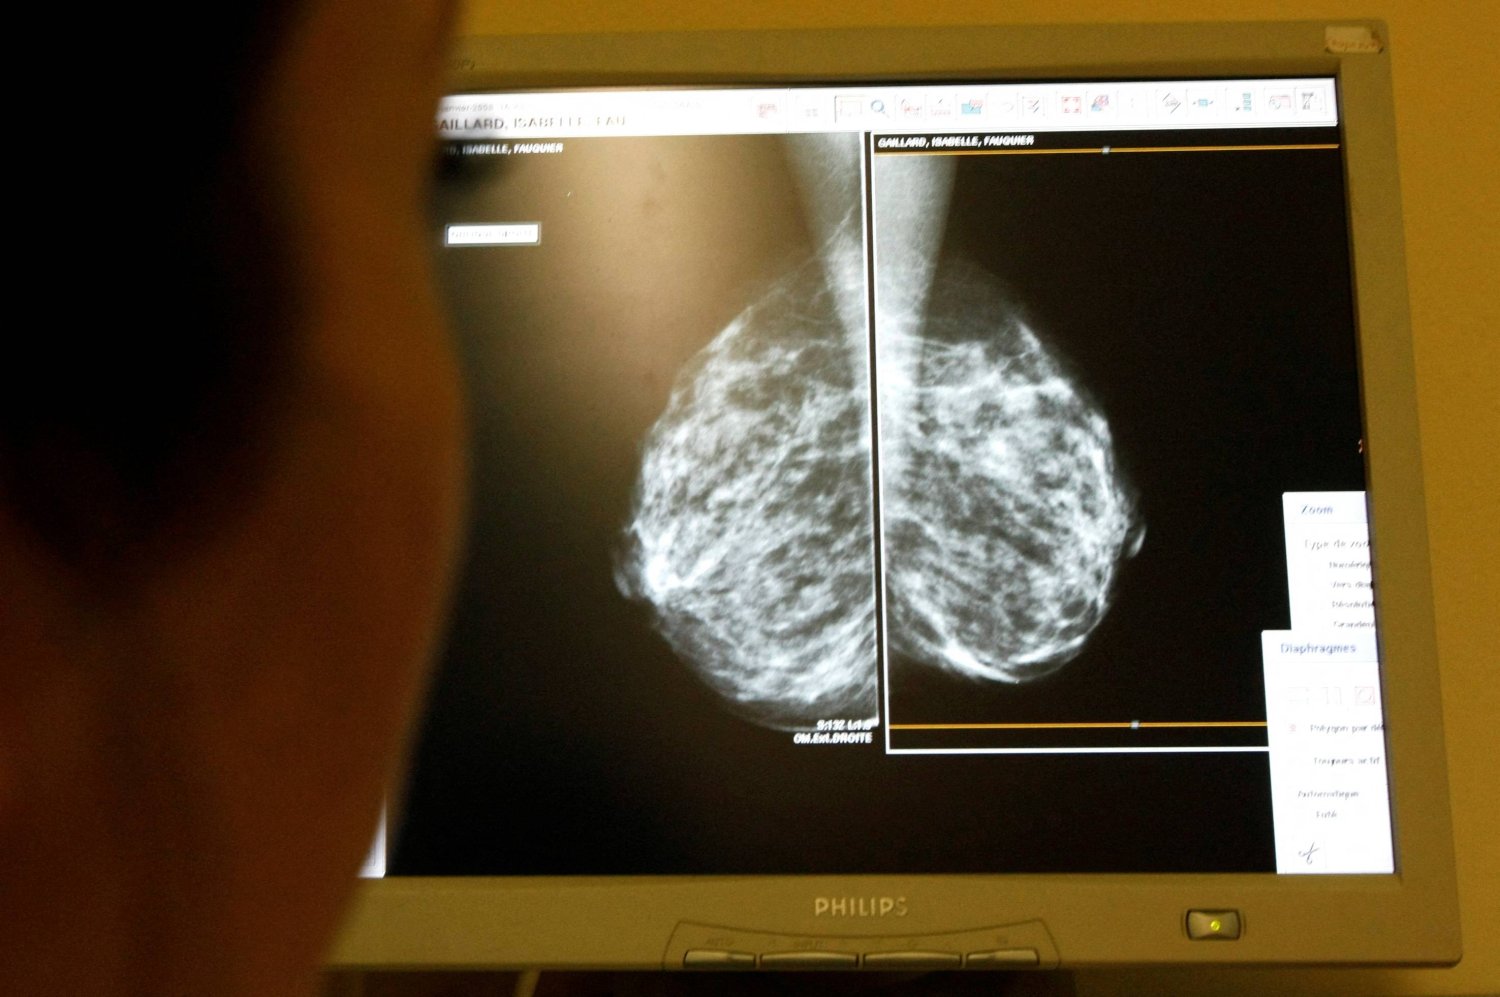

النساء تحت سن الأربعين اللاتي يصبن بسرطان الثدي أكثر عرضة للإصابة بشكل عدواني بشكل خاص من المرض المعروف باسم سرطان الثدي السلبي الثلاثي. ويرتبط هذا بقوة بالطفرة الموروثة في جين «BRCA1».

تقول بيرنا: «إذا كان هناك تاريخ عائلي للإصابة بسرطان الثدي، فيجب على النساء البدء في التحقق من وجود كتل بين عمر 25 أو 30 عاماً». وتابعت: «في حال ملاحظة أي شيء مثير للقلق، فلا حاجة إلى إجراء تصوير الثدي بالأشعة السينية. بالنسبة لامرأة شابة، فإن إجراء فحص بسيط بالموجات فوق الصوتية يكفي للكشف عن أي مشاكل».

يعد تشخيص المثانة والبروستاتا شائعاً جداً عند الرجال، بينما لا يزال سرطان الثدي يشكل 21 في المائة من تشخيصات السرطان لدى النساء فوق سن الـ75 عاماً. ولا يزال سرطان الرئة والأمعاء منتشراً بشكل كبير أيضاً.

إحدى المزايا القليلة للتقدم في السن هي أنه إذا تم تشخيص الإصابة بأي شكل من أشكال السرطان، فمن المرجح أن تكون أقل عدوانية. تشير بيرنا إلى أن أحد أسباب توقف برنامج فحص الثدي التابع لهيئة الخدمات الصحية الوطنية عند سن السبعين هو أن أي امرأة يتم تشخيص إصابتها بسرطان الثدي في هذا العمر تكون أقل عرضة للإصابة بسرطان عدواني.